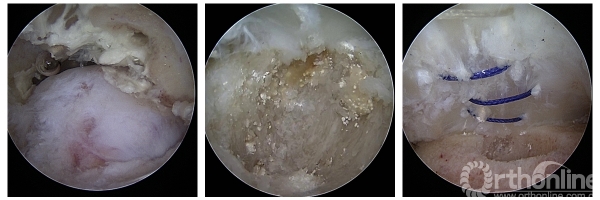

在两天的会议中,成功完成了11台手术,包括4台膝关节韧带重建、2台膝关节内侧骨关节炎单髁置换、1台肩关节前方复发性不稳定改良Bristow稳定术,1台巨大肩袖撕裂SCR修补、1台肩肩胛下肌冈上肌撕裂修补、1台跟腱痛风性腱病伴撕裂清理修补、1台距骨骨囊肿关节镜下清理植骨。

手术病例分享:

△手术名称:肩关节前方复发性不稳定改良Bristow稳定术 术者:崔国庆教授

△手术名称:前后交叉韧带重建 术者:李箭教授、张文涛教授(三台手术)

△手术名称:巨大肩袖撕裂 上关节囊重建 术者:丁少华教授

△手术名称:肩胛下肌、冈上肌撕裂修补 术者:李瑾教授